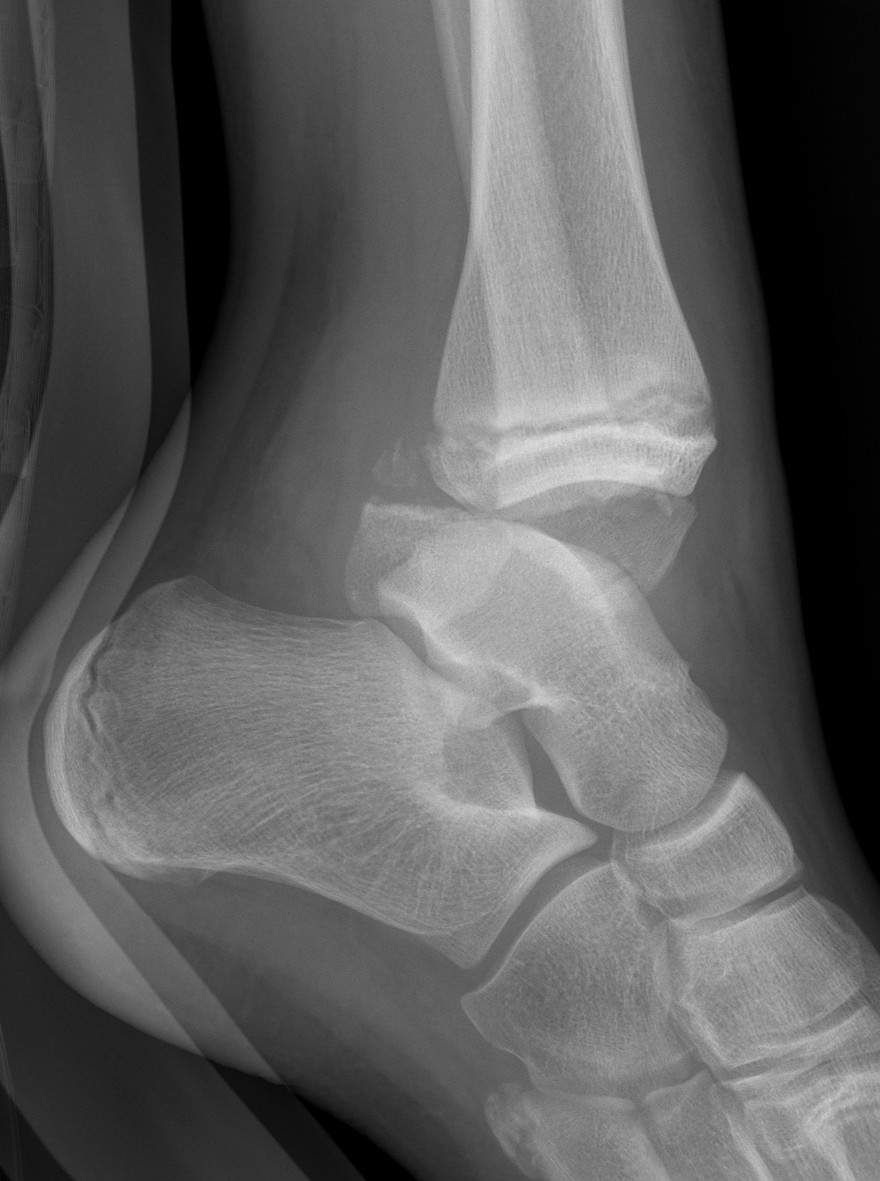

| SH III distal tibia / Tillaux | Triplanar fracture |

![]() |

| Low risk growth arrest / physeal bar | 1% growth arrest as adolescent patients |